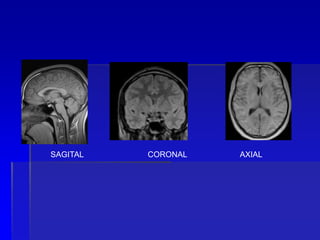

 Quais são os planos de corte

SAGITAL CORONAL AXIAL